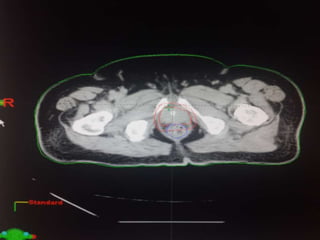

RTOG GU Consensus on pelvic LN CTV volumes:

 Commence contouring the pelvic CTV LN volumes at the L5/ S1

interspace (the level of the distal common iliac and proximal

presacral lymph nodes).

 Place a 7-mm margin around the iliac vessels connecting the

external and internal iliac contours on each slice, carving out

bowel, bladder, and bone.

 Contour presacral lymph nodes from S1 through S3, posterior

border being the anterior sacrum, and anterior border

approximately 10 mm anterior to the anterior sacral bone

carving out bowel, bladder, and bone.

 Stop external iliac CTV lymph node contours at the top of the

femoral heads (bony landmark for the inguinal ligament).

 Stop contours of the obturator CTV lymph nodes at the top of

the symphysis pubis.

Our unit decide to treat:

 Prostate + S.V & prophylactic Pelvic LNs in

phase1

 Prostate + S.V phase 2

 Delineation of our unit illustrated in the

following slides:

RTOG GU Consensuson pelvic LN CTV volumes:  Commence contouring the pelvic CTV LN volumes at the L5/ S1 interspace (the level of the distal common iliac and proximal presacral lymph nodes).  Place a 7-mm margin around the iliac vessels connecting the external and internal iliac contours on each slice, carving out bowel, bladder, and bone.  Contour presacral lymph nodes from S1 through S3, posterior border being the anterior sacrum, and anterior border approximately 10 mm anterior to the anterior sacral bone carving out bowel, bladder, and bone.  Stop external iliac CTV lymph node contours at the top of the femoral heads (bony landmark for the inguinal ligament).  Stop contours of the obturator CTV lymph nodes at the top of the symphysis pubis.

Our unit decideto treat:  Prostate + S.V & prophylactic Pelvic LNs in phase1  Prostate + S.V phase 2  Delineation of our unit illustrated in the following slides: